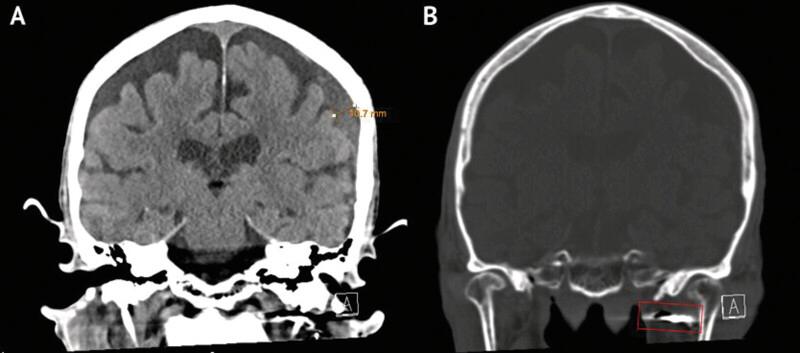

CASE PRESENTATION

A 90-year-old male presented after 6 days of slurred speech and severe headache. A head computed tomography (CT) revealed a left-sided 13-mm subdural hemorrhage, and neck CT angiography revealed left internal carotid artery stenosis at 50%. The carotid stenosis was treated with a standard carotid endarterectomy at the carotid bulb. Despite direct catheterization of the external carotid artery, selective catheterization of the MMA was not feasible. Instead, coils were placed in the left internal maxillary artery spanning the left MMA origin, and the right MMA was selectively embolized using a standard transradial approach. Postoperative CT showed a reduction in subdural hematoma (SDH) size, and the patient was discharged in stable condition on postoperative day 6.

一名90岁男性在出现言语含糊和严重头痛6天后就诊。头部计算机断层扫描(CT)显示左侧有13毫米的硬膜下出血,颈部CT血管造影显示左侧颈内动脉狭窄50%。在颈动脉球部对颈动脉狭窄进行了标准的颈动脉内膜切除术治疗。尽管直接对颈外动脉进行了插管,但对MMA进行选择性插管不可行。取而代之的是,将线圈置于跨越左侧MMA起源处的左上颌动脉内,并采用标准的经桡动脉途径对右侧MMA进行选择性栓塞。术后CT显示硬膜下血肿(SDH)大小减小,患者在术后第6天病情稳定出院。